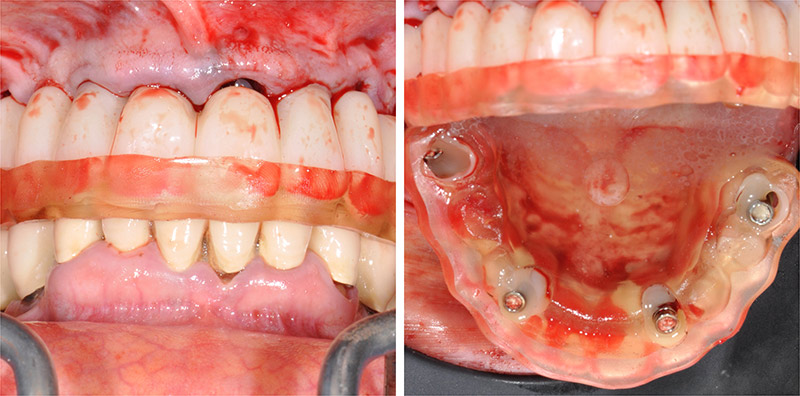

Intervention :

Fig. 23 : les différents guides et la prothèse transitoire immédiate produits par Createch sont préparées à disposition du chirurgien.

Fig. 24 et 25 : le guide de forage des emplacements des clavettes s’appuyant sur les structures initiales est utilisé en premier avec un foret spécifique.

Fig. 26 : les dents sont extraites, un large lambeau est ouvert puis le guide de résection osseuse est inséré et claveté dans les emplacements précédemment forés.

Fig. 27 : la résection osseuse est réalisée en respectant le plan du guide en accord avec la planification ; dans ce cas par piezo-chirurgie.

Fig. 28 : le guide de forage et d’insertion des implants est empilé sur le guide de résection laissé en place.

Fig. 29 : toujours sans toucher au guide résection, une fois les implants mis en place, les piliers prothétiques sont vissés.

Fig. 30 : enfin, la restauration transitoire est empilée sur le guide de résection pour être solidarisée en bouche aux gaines provisoires vissées sur les piliers.

(NDLA : l’intervention est réalisée sous AG selon la volonté de la patiente ; le temps, en particuliers pour les photos, est compté par les obligations de l’anesthésie ; sans s’en apercevoir la restauration a bougé lors de la prise de la photo et ne reflète pas la réalité de la parfaite adaptation des pièces).

Fig. 31 et 32 : l’assemblage entre la restauration PMMA et les gaines en titane est réalisé avec une colle composite.

Fig. 33 et 34 : la finition est immédiatement et rapidement réalisée au fauteuil pour une mise en place de la prothèse transitoire dès la fin de l’intervention.